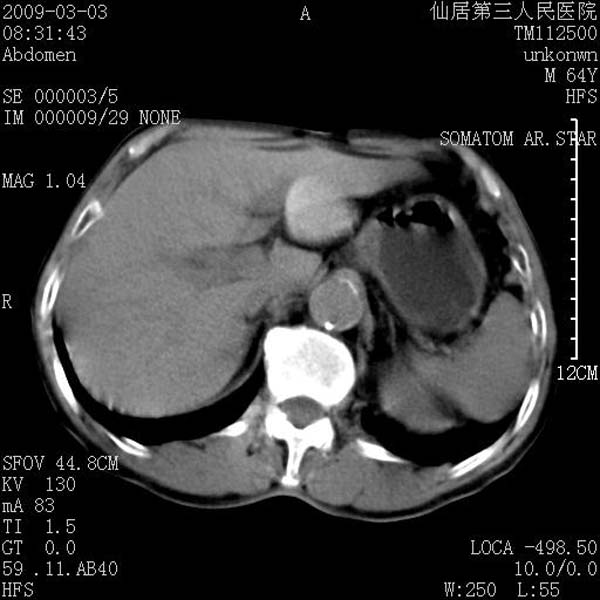

标题: CT18469:男性,64y,体检B超示肝脏低回声肿块,有胃溃疡手术 [打印本页]

患者,男性,64y,体检b超示肝脏低回声肿块,有胃溃疡手术史。

考虑----胃肠道间质瘤可能性大

从平扫及增强的特点来看,支持肝脏腺瘤并出血。

考虑胃间质瘤可能性大。

ct值呢?感觉没强化,象囊性。

考虑肝静脉韧带裂区良性占位性病变(囊肿?)。

考虑肝囊肿并出血可能性大.

考虑高密度囊肿可能性大